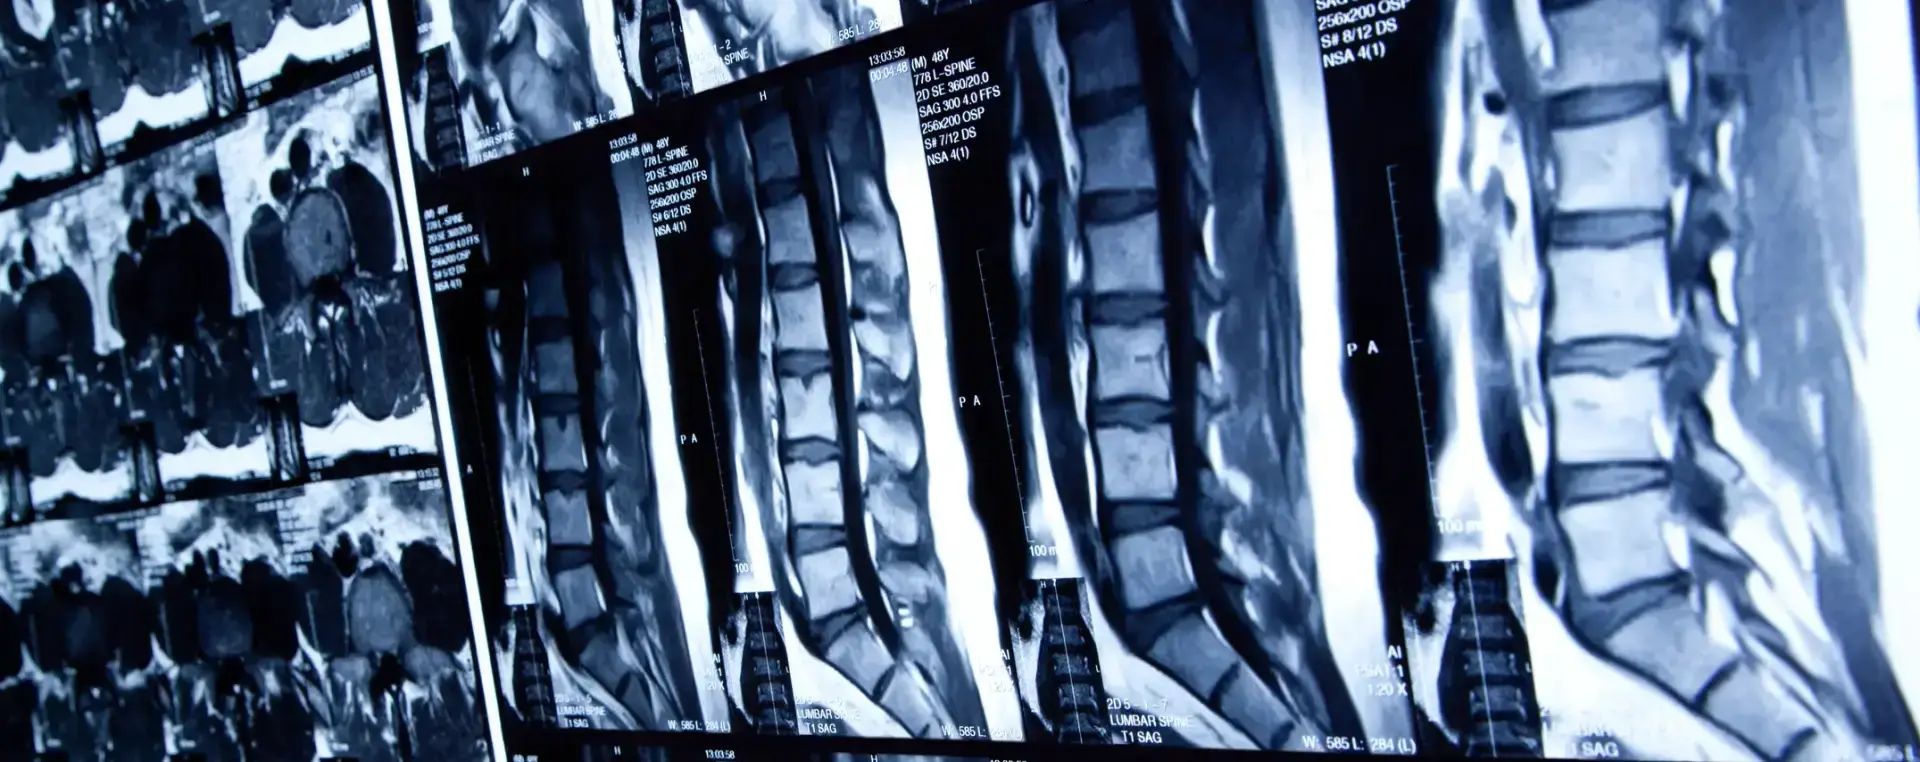

Spinal cord injuries can be caused by damage to any part of a personโs spinal cord or the nerves at the end of the spinal canal. These injuries are catastrophic and can easily cause permanent changes in strength, tactile sensation, and other crucial bodily functions. However, the severity of a spinal cord injury is based on how many nerve connections are severed in an accident and as such they are classified as either complete or incomplete.

Complete spinal cord injury occurs when there is a complete severance of nerve connections from the spine to the brain and all feeling and ability to control movement is lost. Meanwhile, an incomplete spinal cord injury occurs when there is a partial severance of nerve connections and as a result, there is partial motor or sensory function. Depending on the location and the nature of the accident, incomplete injuries are recoverable, but requires extensive physical therapy and possibly surgery.